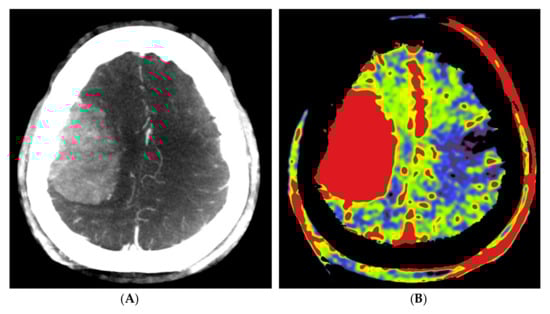

Figure 1.

Example of PBV images pre- and post-embolization with manually drawn regions of interest (ROIs) in a patient with a right frontal convexity atypical meningioma (patient no. 2). Axial post-contrast T1-weighted MRI image (A) shows the tumor with vivid enhancement and intralesional large vessels in a spoke wheel pattern. According to Wen et al. [21], handheld ROIs for PBV value measurements are drawn on PBV images after aortic root contrast injection in axial plane and in sagittal plane before embolization (axial reformation in (C) and sagittal reformation in (D) and after embolization (axial reformation in plane (F), reformation in sagittal plane is not shown) at the level of the largest tumor area. To confirm correct delineation of the PBV measurement area, PBV series were fused with the fill run series (B). Reference PBV measurement on the contralateral side was done using an elliptical ROI in sagittal plane reformation (E).